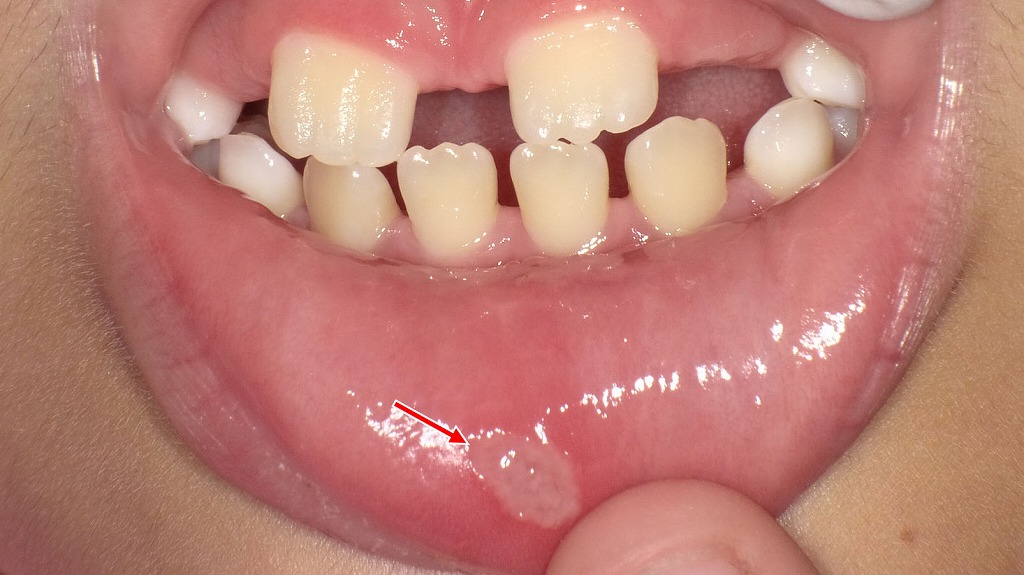

下唇の内側にみられる白っぽい潰瘍は、子どもによくみられる口内炎(アフタ性口内炎)です。食事や会話の際にしみたり痛みを感じることがありますが、多くは1〜2週間ほどで自然に治癒します。痛みが強い場合や、繰り返しできる場合は、小児歯科・歯科医院での相談がおすすめです。

画像には、歯茎(歯肉)にできたアフタ性口内炎の典型的な所見が確認できます。

🔍 観察ポイント

- 部位:下顎の臼歯部の歯肉(歯ぐき)

- 大きさ:数ミリ(約3〜5mmほど)

- 色調:中央が白〜黄白色、その周囲が赤く炎症性に変化

- 形状:境界明瞭な円形〜楕円形の浅い潰瘍

- 周囲組織:軽度の発赤(炎症)があり、アフタ性潰瘍の典型像

矢印で示されている白い部分は上皮が欠損し、フィブリンという白い膜が張った状態で、アフタ性口内炎の特徴と一致します。

🦷 考えられる疾患

アフタ性口内炎(アフタ性潰瘍)

歯肉にも発生することがあり、以下が誘因となりやすいです:

- 歯ブラシの刺激

- 食事による摩擦

- ストレス、疲労、免疫低下

- 栄養不足(特にビタミンB群)

😣 痛みの特徴

- 食事、発音、歯磨きの際に痛みが出やすい

- 歯肉は動かない部分のため、痛みは比較的限局するが、物理刺激に弱い

- 数日~2週間程度で自然治癒することが多い

🧪 注意が必要な場合

以下の場合はアフタ以外の疾患の可能性も考慮します:

- 2週間以上治らない

- 周囲に硬さ(硬結)がある

- 同じ場所に何度も再発

- 病変が急激に大きくなる

💡 ケア方法

- 刺激物(辛い物、熱い物、酸味)を控える

- 歯磨きは柔らかいブラシで優しく

- ビタミンB群を補給

- 市販のステロイド軟膏・アフタパッチを使用

- 歯科でのレーザー治療は痛みを軽減